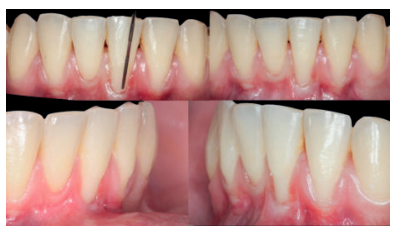

El examen clínico periodontal reveló la presencia de recesión gingival de 5 mm en el diente 31 con una profundidad de sondaje vestibular de 2 mm (perdida de inserción clínica de 7 mm). Presentaba inflamación gingival, además de un frenillo labial inferior insertado en el margen apical de la recesión gingival. El tejido queratinizado faltaba por completo a nivel del diente con recesión (Figura 1). Debido a que el defecto gingival se extendía más allá de la línea mucogingival, así como a la presencia de malposición dentaria, la recesión se categorizó como clase III de Miller6 y RT2 de Cairo7 .

Previamente a la intervención, la paciente se enjuagó durante 1 minuto con un colutorio de clorhexidina. La técnica quirúrgica comenzó con la preparación del lecho receptor, para ello se realizó una incisión sulcular a espesor parcial a nivel de la recesión, se continúo diseccionando apical y lateralmente, extendiéndose de 3 a 5 mm de la recesión para permitir la entrada del ITC y su estabilización. Posteriormente, se realizó una incisión en el fondo de vestíbulo, dejando un puente de tejido que servirá para un doble aporte sanguíneo al injerto (Figura 2).

Se realizó control a la semana de la intervención (Figura 4) y tras 15 días se retiró la sutura, observando la revascularización del injerto y la epitelización del área cruenta apical al sobre (Figura 5). Se realizó seguimiento al mes (Figura 6), a los 3 meses (Figura 7) y al año y medio del procedimiento (Figura 8).